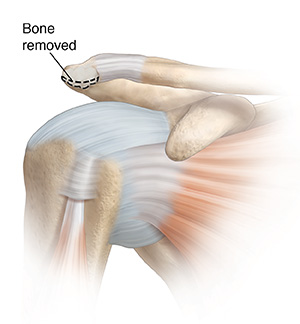

The type of surgery you have depends on your shoulder problem. Surgery can remove the bursa if it is swollen. If the coracoacromial ligament is tight, it may be released. If the acromion is hooked or has bone spurs, a part of it may be taken out. Before surgery, you’ll be given medicine to keep you free from pain. There are 2 different types of surgery. These are:

| A portion of the acromion may be removed. |